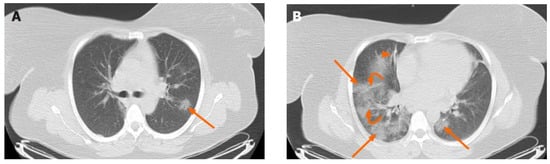

1. Introduction

2.1. Data Collection and Pre-Processing